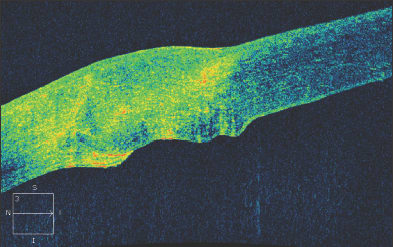

The results of surgical interventions can also be documented, including the position of Descemet's stripping endothelial keratoplasty buttons, glaucoma tube shunts or intraocular lenses. After penetrating keratoplasty, the graft-host interface can be evaluated as seen in this patient with a traumatic corneal laceration, resulting in an emergent penetrating keratoplasty and suboptimal graft-host alignment (Figure 7). Filtering blebs after trabeculectomy can be evaluated, and subconjunctival filtration can be demonstrated (Figure 8).

Figure 7. An irregular graft-host interface following penetrating keratoplasty.

Figure 8. A filtering bleb following trabeculectomy. Fluid is present beneath the conjunctiva and Tenon's fascia.

After DSEK, the position and apposition of the donor endothelial button can be evaluated. In Figure 9a, the endothelial button can be seen to be non-adherent to the corneal stroma, with associated epithelial bullae. After several months, the endothelial button has become fully adherent, and the epithelial fluid has resolved (Figure 9b). In Figure 10, we see a patient who has undergone combined penetrating keratoplasty and tube shunt implantation, and the tube position, while somewhat anterior, is confirmed to be free of corneal touch. The graft-host junction is visualized and the corneal stroma and endothelium anterior to the tube tip appear normal.

Figure 9. Shortly following Descemet's stripping endothelial keratoplasty, the endothelial button can be seen to be non-adherent to the corneal stroma, with associated epithelial bullae (Fig. 9a, above). After several months, the endothelial button has become fully adherent, and the epithelial fluid has resolved (Fig. 9b, below).

Figure 10. Anterior segment OCT of a patient who has undergone combined penetrating keratoplasty and tube shunt implantation. The tube position, while somewhat anterior, is confirmed to be free of corneal touch.